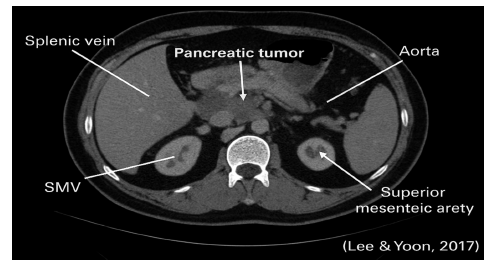

Figure 3:A mass in the pancreatic head compressing nearby vessels revealed by a CT imaging. Source: Lee and Yoon [15].

Computed Tomography (CT) is the first-line imaging technique. It provides high-resolution images of tumour size, vascular involvement and metastasis. Figure 3 shows a CT scan of a pancreatic tumour, revealing its location and relationship to surrounding vessels [15].